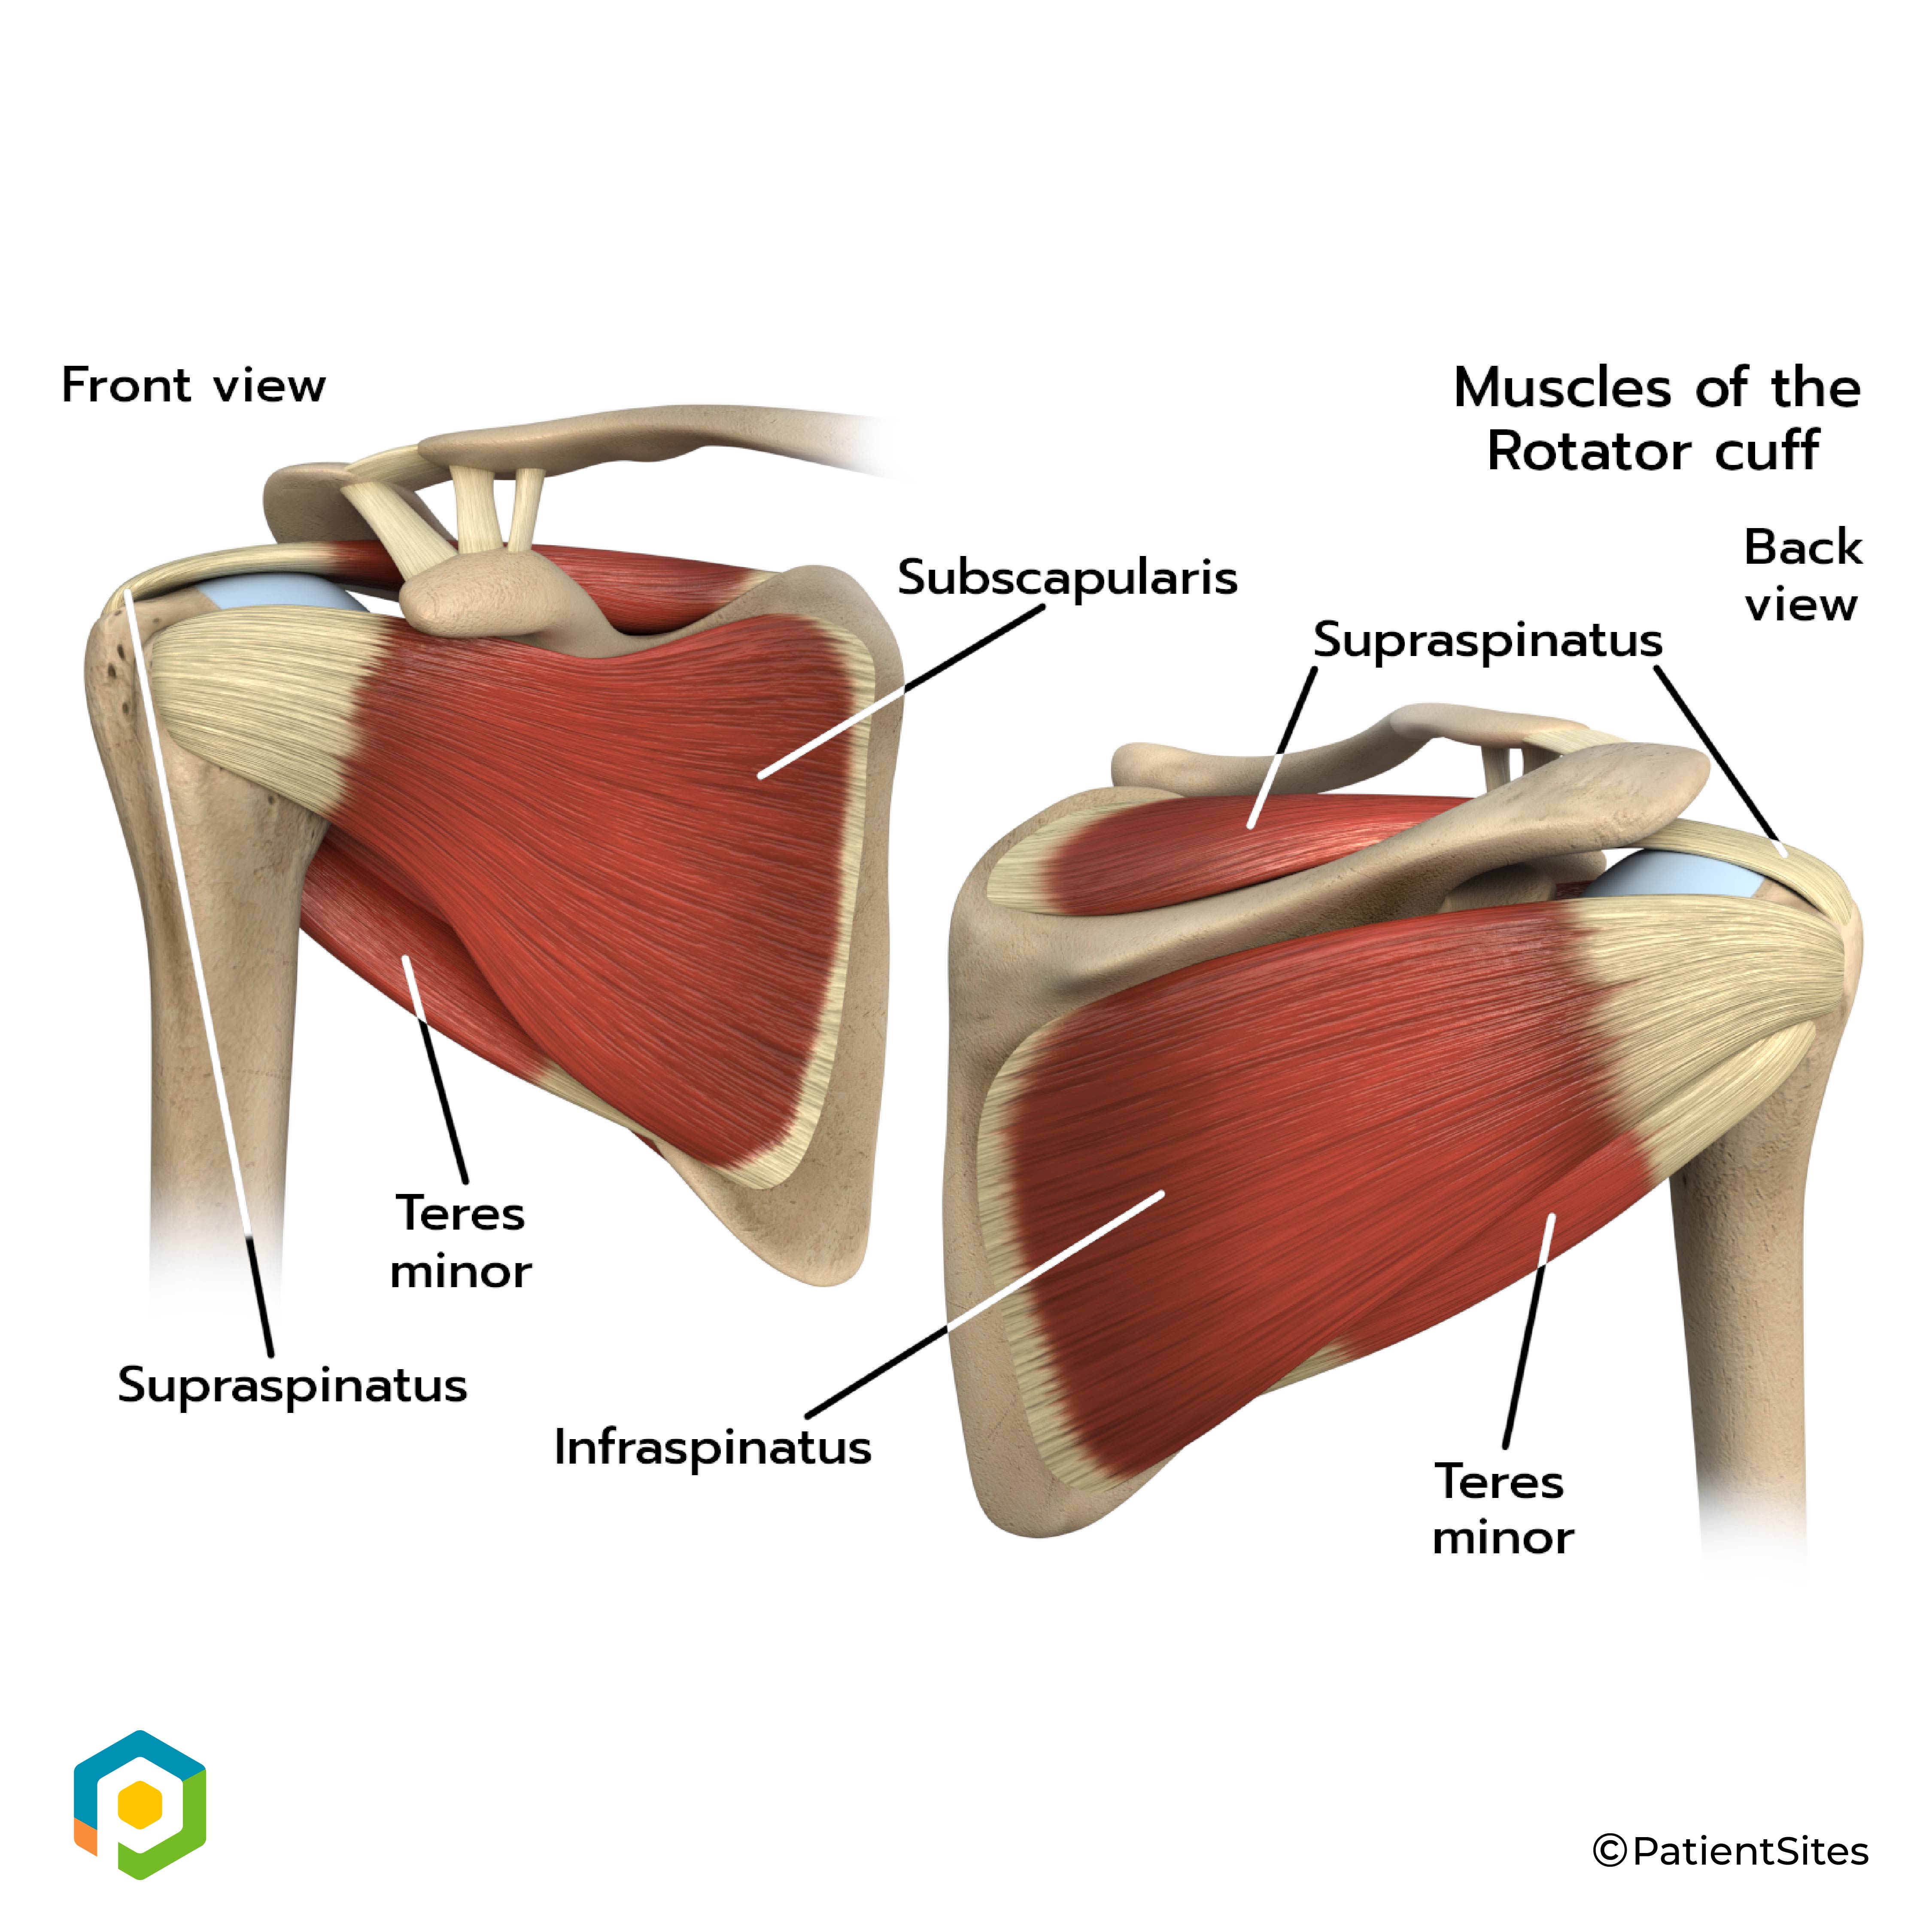

The rotator cuff connects the humerus to the scapula. The rotator cuff is formed by the tendons of four muscles: the supraspinatus, infraspinatus, teres minor, and subscapularis.

Rotator Cuff

Tendons attach muscles to bones. Muscles move the bones by pulling on the tendons. The rotator cuff helps raise and rotate the arm.

As the arm is raised, the rotator cuff also keeps the humerus tightly in the socket of the scapula, the glenoid. The upper part of the scapula that makes up the roof of the shoulder is called the acromion.

At first, we will use various treatments to calm inflammation, including heat and ice. Our physical therapist will also use hands-on treatments and stretching to help restore full shoulder range of motion. Any problems with shoulder and upper back posture will need to be corrected first to improve alignment and shoulder biomechanics. Improving strength and coordination in the rotator cuff and shoulder blade muscles lets the humerus move in the socket without pinching the tendons or bursa under the acromion. Although time required for recovery varies, as a guideline, you may need physical therapy treatments for four to six weeks before you get full shoulder motion and function back.

It is important to maintain the strength in the muscles of the rotator cuff. These muscles help control the stability of the shoulder joint. Strengthening these muscles can actually decrease the impingement of the acromion on the rotator cuff tendons and bursa. Our physical therapist can also evaluate your workstation or the way you use your body when you do your activities and suggest changes to avoid further problems.